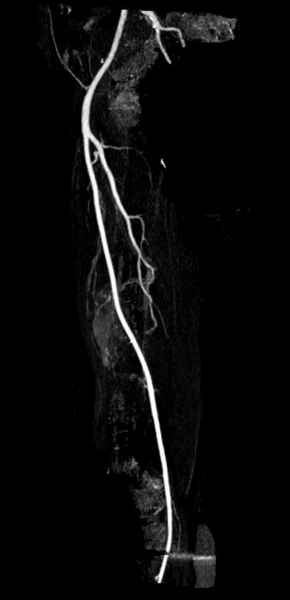

В зависимости от характера опухоли некоторые патологические переломы имеют риск кровотечения во время операции. Множественные литературные данные подтверждают, что надо проявить осторожность при интрамедуллярном остеосинтезе при неизвестных опухолях, особенно где имеется подозрение на Renal Cell Carcinoma. (RCC- hypernephroma) http://www.bonetumor.org/tumors/pages/page64.html

Со слов, больная ничем не болела, только последние 3 месяцев чувствовала боли в бедренной области. КТ брюшной полости подтвердил увеличенную правую почку. (5-6)

Для предупреждения кровотечения во время рассверливания, за день до операции провели эмболизацию сосудов питающий метастаз. http://radiology.rsnajnls.org/cgi/reprint/150/3/673.pdf (7-11, 12-15-16)